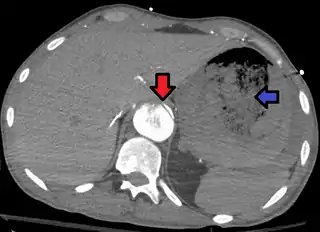

![]() Fístula arortoentérica y disección aórtica de la aorta torácica. La flecha indica la solapa en la aorta. La heterogeneidad es sangre en el estómago. | ||